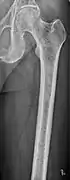

X-ray of the forearm, with lytic lesions

Femur with multiple myeloma lesions

Same femur before myeloma lesions for comparison